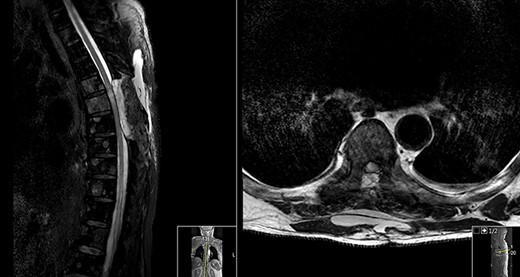

MRI done at this time showed a reduction in the T2 hyperintensity seen in both previous post-op MR scans (Fig. 3).